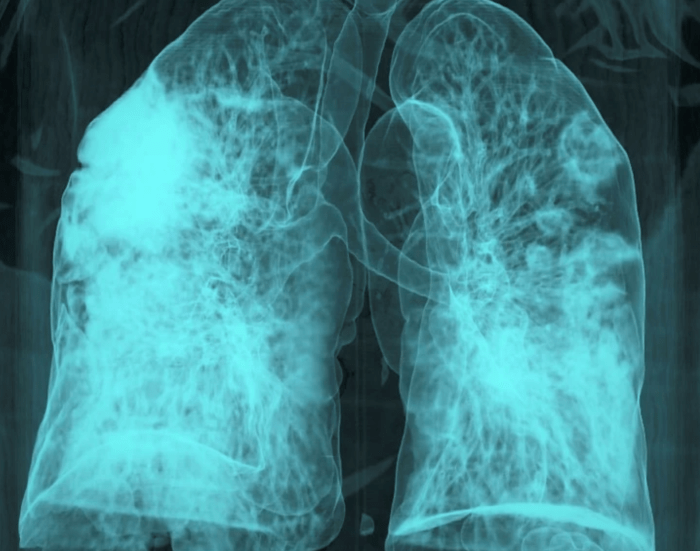

Nhóm của DeGregori đặt câu hỏi: liệu viêm cấp tính do nhiễm trùng hô hấp có thể kích hoạt tế bào ung thư đang ngủ yên hay không? Để kiểm tra, họ biến đổi gen của chuột để phát triển khối u vú giống ở người và cấy các tế bào ung thư ngủ yên vào các mô, bao gồm phổi. Sau đó, họ cho chuột nhiễm SARS-CoV-2 hoặc virus cúm.

Chỉ vài ngày sau, các tế bào ung thư ngủ yên trong phổi chuột bắt đầu hoạt động mạnh, nhân lên và hình thành ổ di căn. Nhưng nguyên nhân không phải do mầm bệnh trực tiếp, mà là do interleukin-6 (IL-6) – một phân tử miễn dịch quan trọng giúp cơ thể thúc đẩy phản ứng viêm để chống lại nhiễm trùng cũng như thúc đẩy chữa lành vết thương. Khi nhóm nghiên cứu tạo ra chuột thiếu IL-6, các tế bào ngủ yên không nhân lên nhanh như trước.